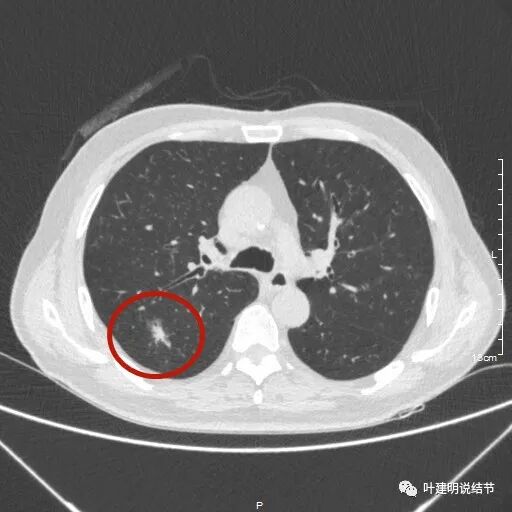

肺癌的影像学鉴别诊断实例:哪些不是肺癌

图3 影像学上鉴别肺癌还是很有必要的,某人不体检,万一他之前就有磨

早期肺癌CT图

肺结节影像图片